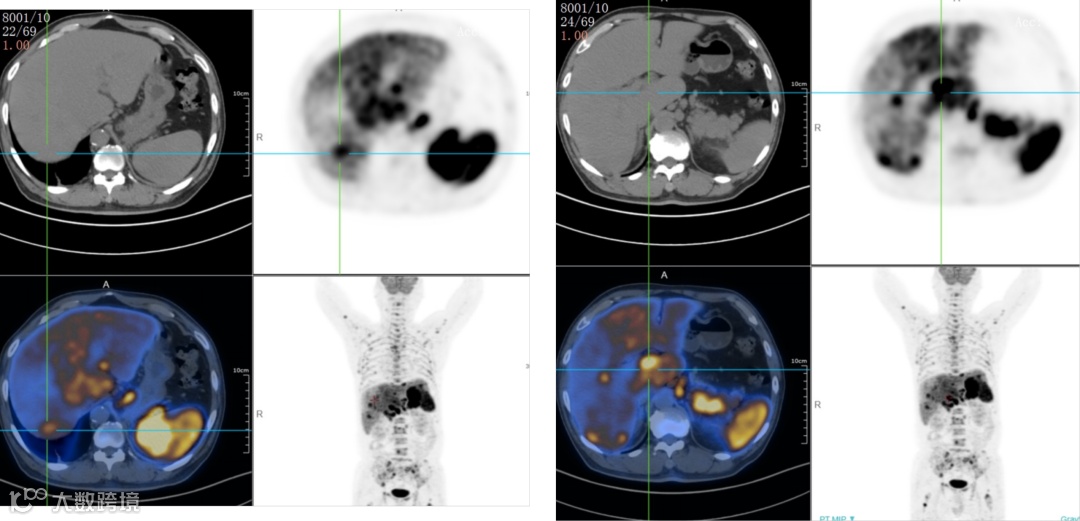

双侧内乳区、膈上、右侧膈肌脚区、肝门区、肝胃间隙、脾门区、腹膜后多发淋巴结,肝脾肿大,代谢增高;脊柱多个椎体及部分附件、双侧肱骨、双侧肩胛骨、双侧锁骨、双侧多根肋骨、胸骨、骨盆诸组成骨、双侧股骨上段多发代谢异常增高灶。